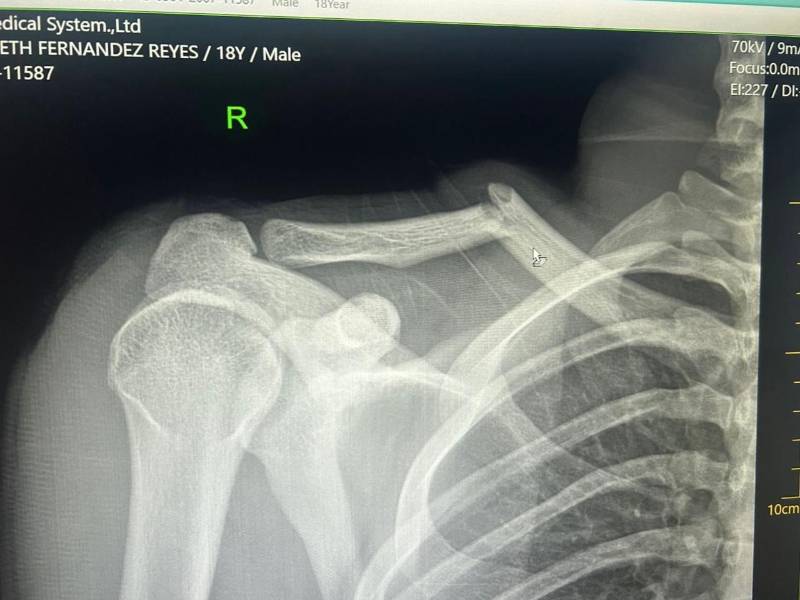

Luego de los estudios realizados, LA PRENSA conoció que el joven futbolista del conjunto verdolaga sufre una fractura de clavícula en el hombro derecho, producto de un fuerte choque con Elvin Casildo, donde el defensor del Victoria lo frenó con fuerza desmedida.

El tiempo estimado de recuperación para este tipo de lesión es de entre 10 y 12 semanas, es decir, entre dos y tres meses fuera de las canchas. Esto significa que Fernández prácticamente se perderá lo que resta del torneo Clausura 2026 de la Liga Nacional de Honduras.

Los Rayos-X que le realizaron a Jaylor Fernández tras el partido ante el Victoria.